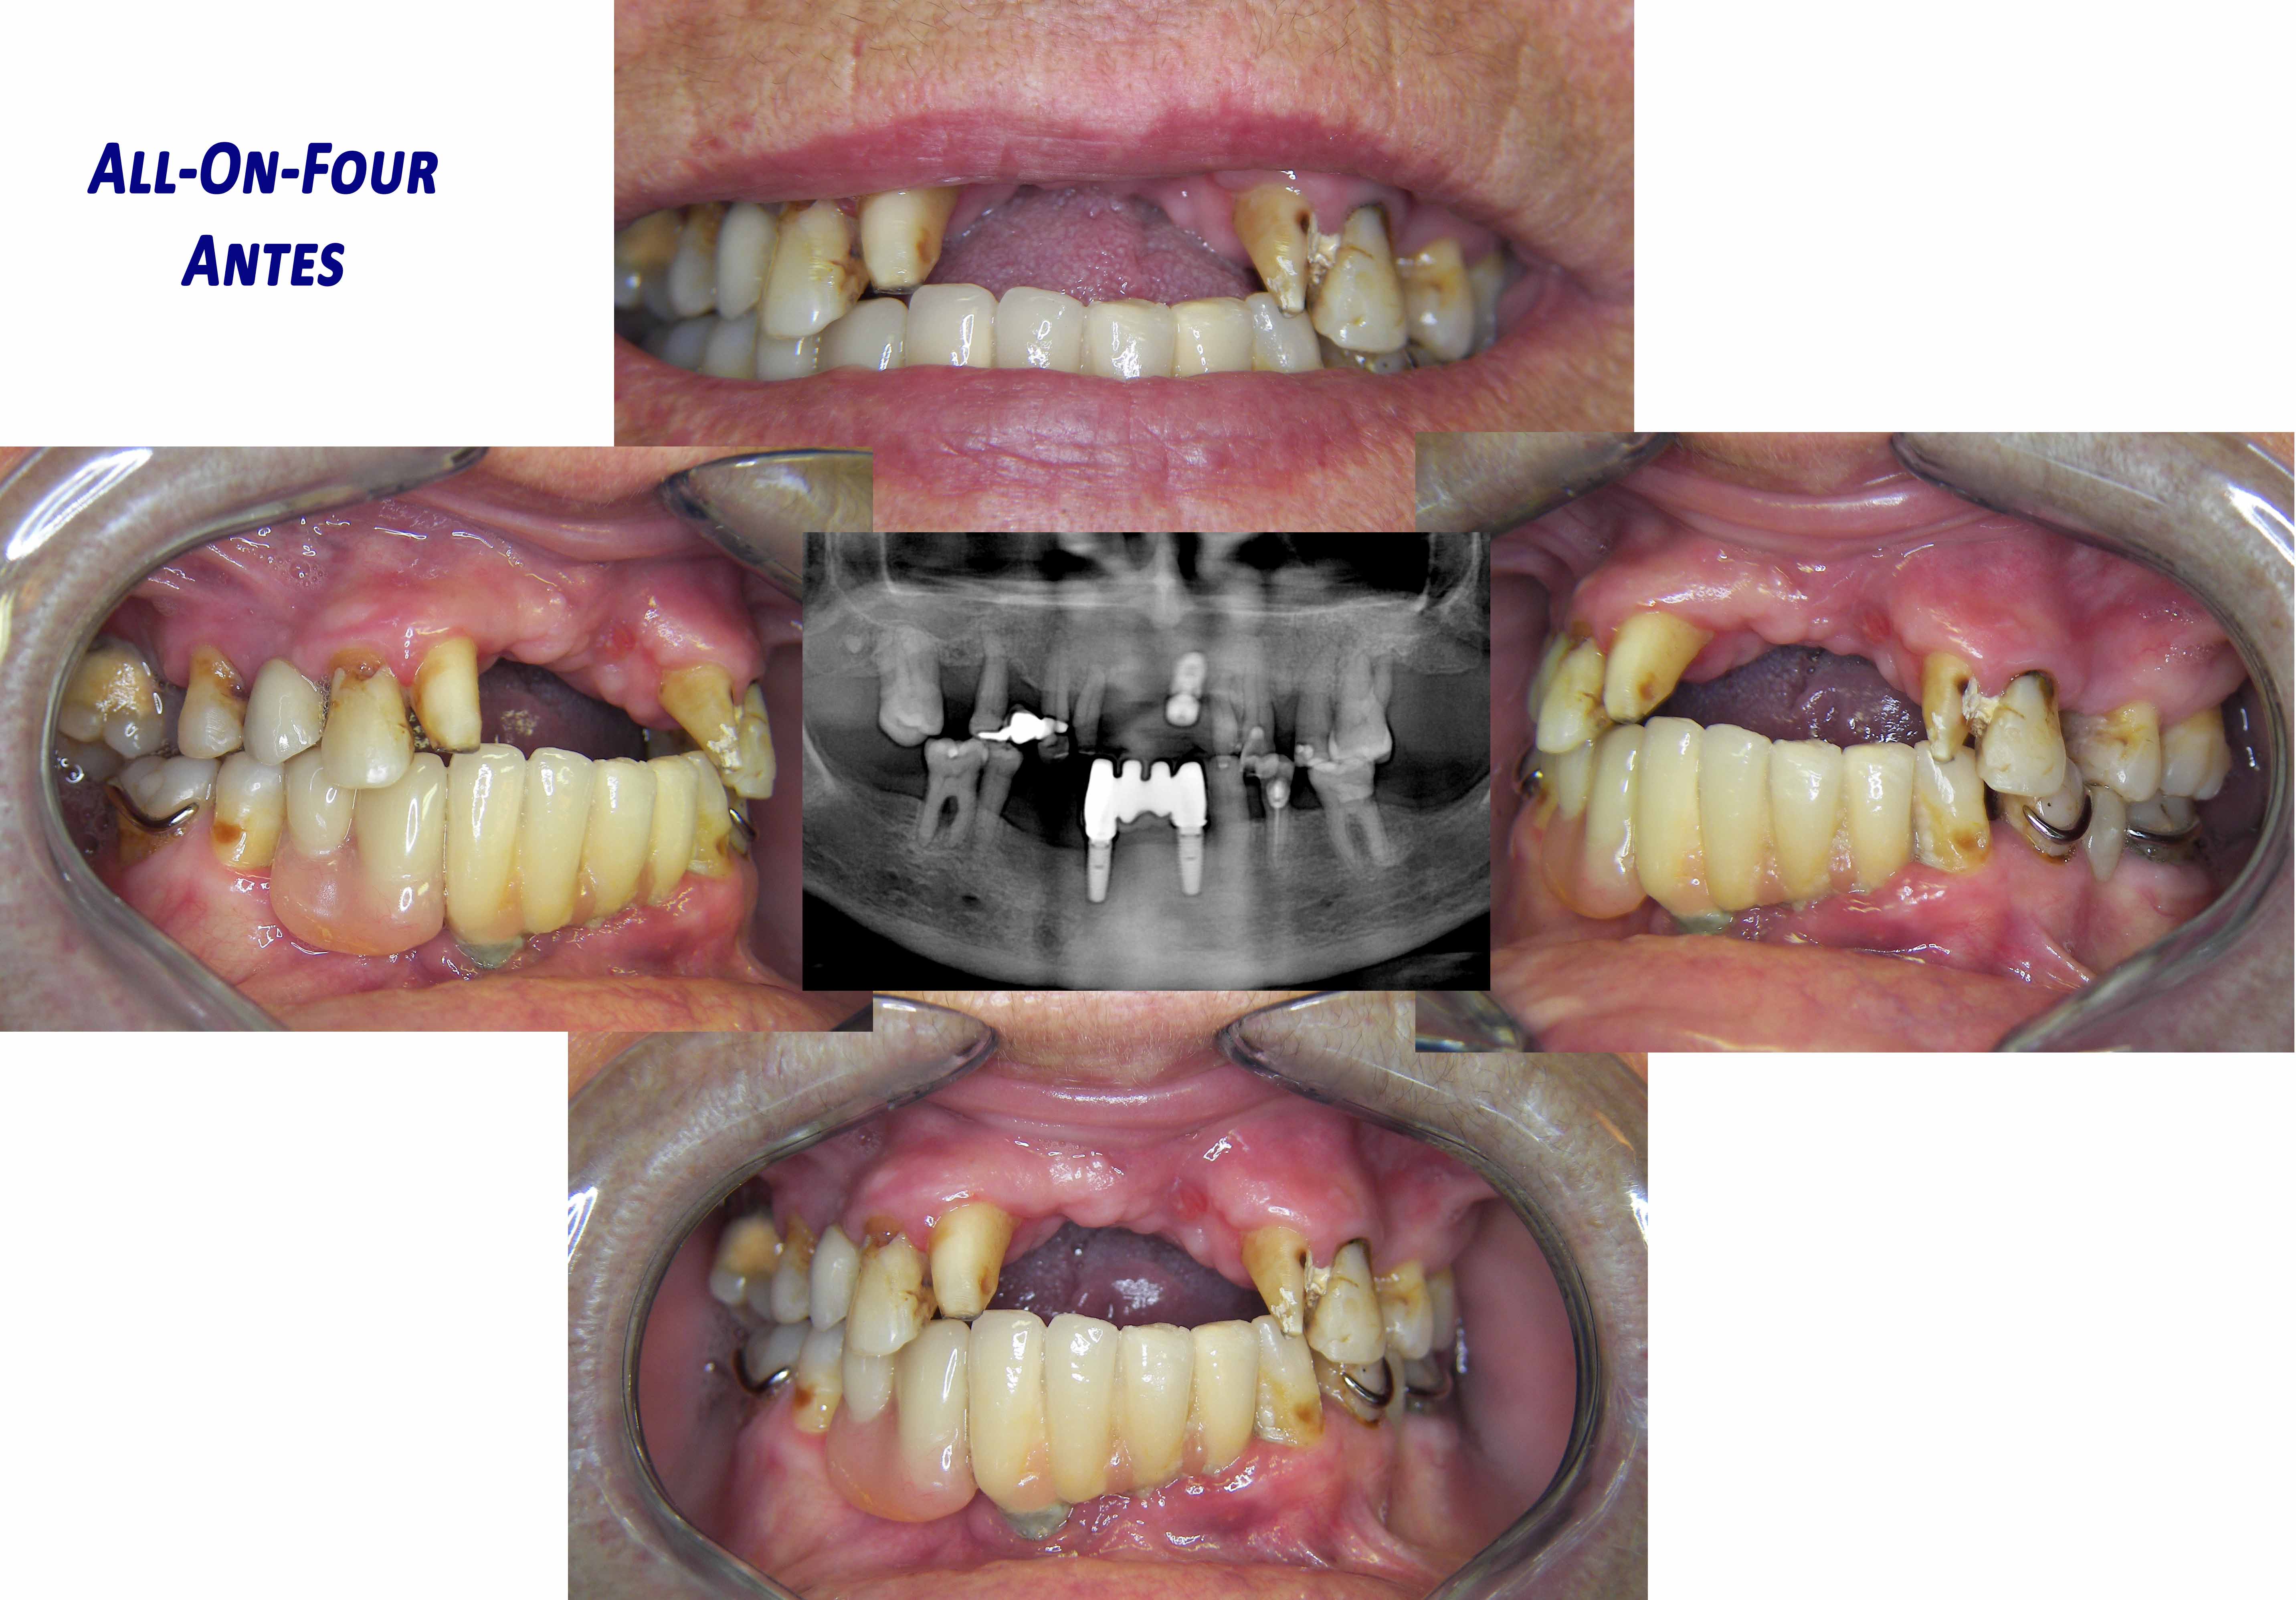

All-On-Four

Total prostheses over implants on both archs. It can be done on only one arch.

This protocol that uses 4 implants per arch allows that temporary fixed teeth are placed in the same day as the surgery is done.

The patient maintains the aesthetics and chewing functions from day 1.

The more functional and aesthetically better looking permanent prostheses are built around 6 months after the surgery to allow a complete healing of the bone and gums.